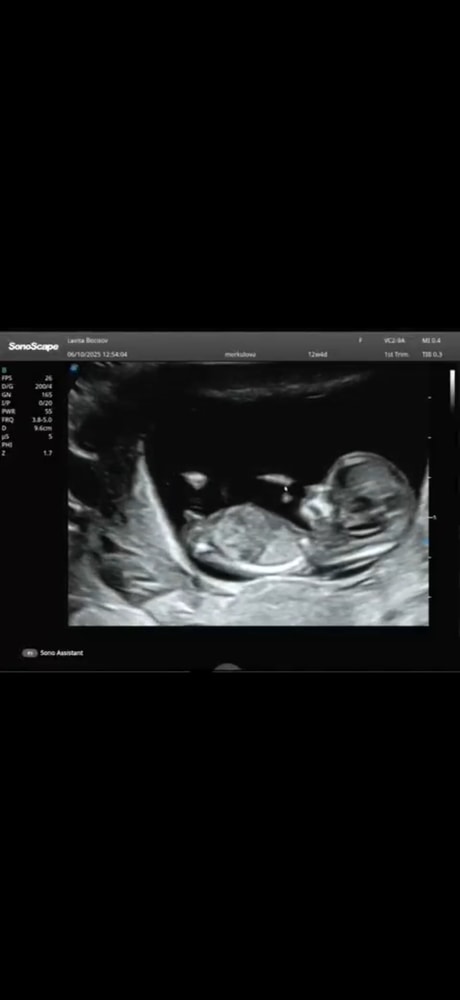

Подскажите на кого похоже ? Мальчик или девочка ?

Пол малышаСрок 12 недель . Скрины с видео , при разном ракурсе половой бугорок меняется